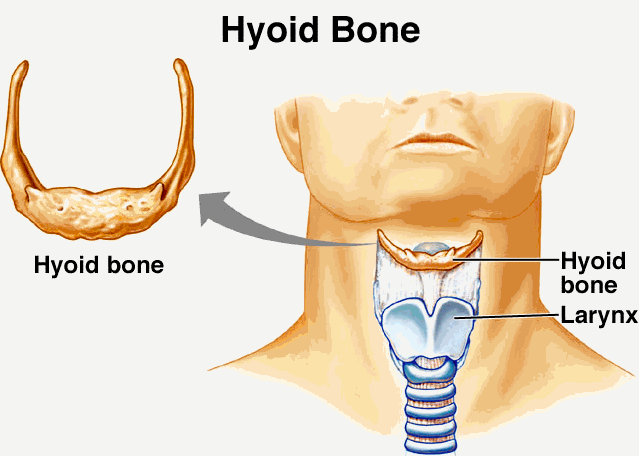

▼舌骨:舌骨是舌頭中的骨頭,讓舌頭可以維持在改在的位置,並讓人類可以控制舌頭而發聲。這塊骨頭完全依靠韌帶和肌肉連接,並沒有和身上任何一塊骨頭聯繫著。